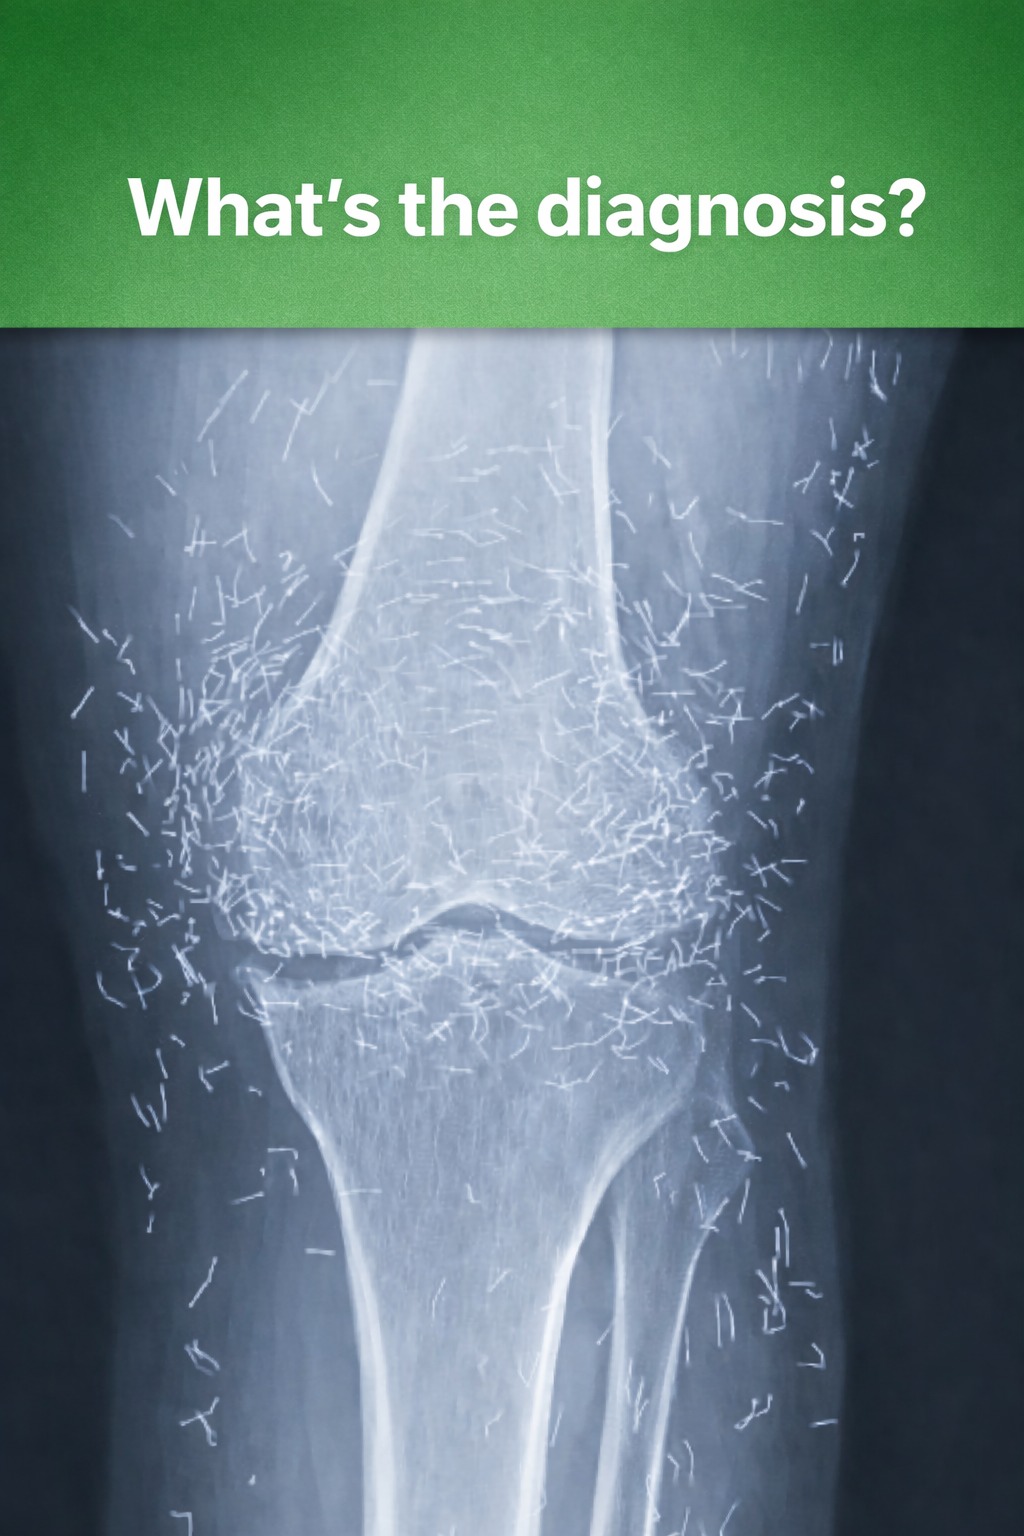

When a 65-year-old woman in South Korea visited doctors for chronic knee pain, they discovered something unexpected — dozens of tiny gold acupuncture needles embedded around her knees. The unusual finding quickly drew attention in the medical world. The woman had long struggled with osteoarthritis, a condition that wears down joint cartilage and causes stiffness, swelling, and persistent pain. Everyday activities like walking, climbing stairs, or bending had become difficult.

Traditional painkillers and anti-inflammatory medications provided little relief and caused stomach discomfort, so she turned to acupuncture, a traditional treatment used to reduce pain. In some cases, tiny gold needles or threads are intentionally left in the body to provide continuous stimulation. However, medical experts warn that leaving foreign objects inside the body can pose risks.

Embedded needles may lead to inflammation, infection, or abscesses, and the body may react by forming fibrous tissue around them. Doctors also note that such objects can complicate medical imaging. The presence of metal may obscure X-ray results and can make MRI scans dangerous, as metal fragments could move and damage nearby tissue or blood vessels.